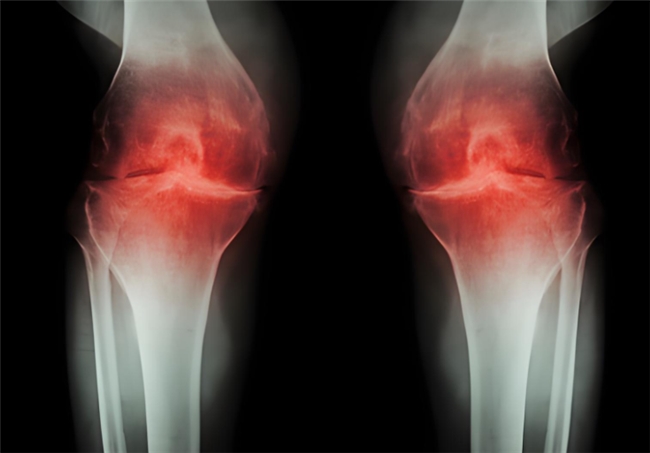

冬季清晨的公园与跑道从不缺乏运动者的身影。但对于骨关节炎患者而言,这份坚持背后却隐藏着风险:低温环境下,关节滑液黏滞度增加,软骨弹性下降,不当地晨练反而可能加速软骨磨损。因此,骨关节炎患者冬季晨练务必做好充分保暖与热身,并做到正确、适当的运动。在此基础上,还可在医生指导下服用氨糖来治疗。但它还分盐酸和硫酸氨基葡萄糖胶囊。到底盐酸和硫酸氨基葡萄糖胶囊的作用与功效有何不同?如何选择呢?

盐酸和硫酸氨基葡萄糖胶囊都是氨基葡萄糖类药物,能为关节软骨提供合成原料,在促进软骨基质的修复与再生的基础上,补充关节滑液以减少摩擦,同时通过抑制关节腔内的炎症因子,从多个方面帮助延缓骨关节炎的进展[1],但它们在临床疗效上却存在一定差异。